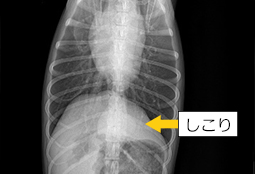

軟部外科は骨や神経以外の柔らかい組織を扱う外科です。避妊去勢手術から体表腫瘍の切除、腹腔内、胸腔内の腫瘍切除まで多くの範囲を含みます。